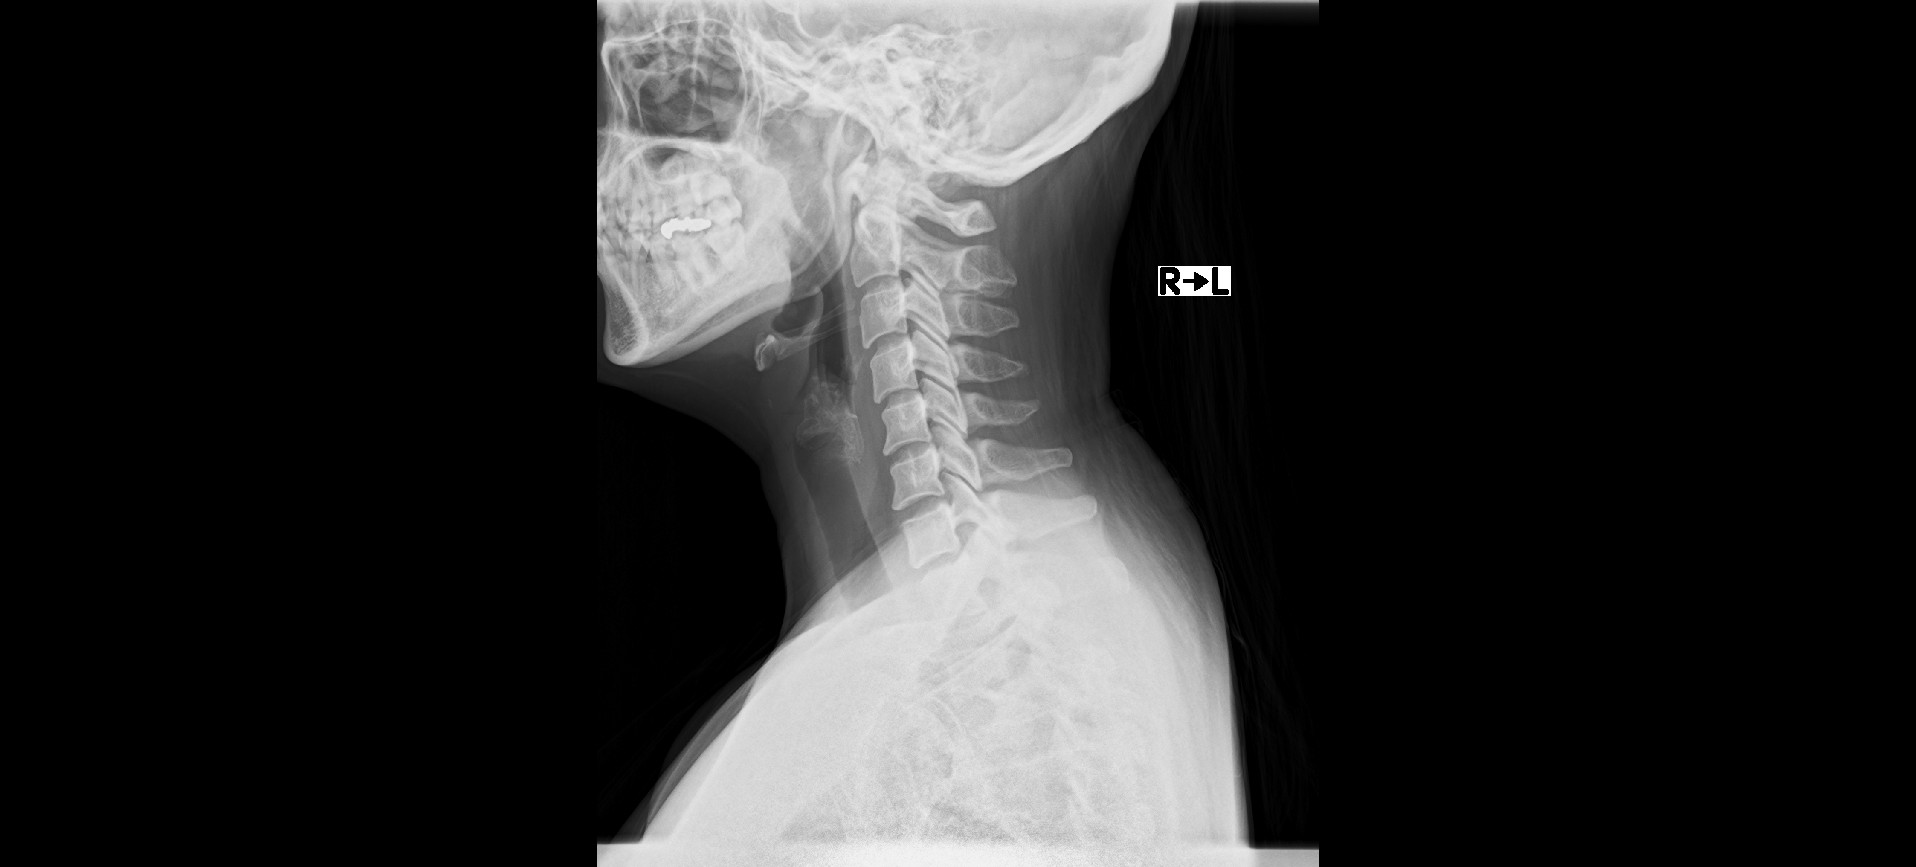

初診時、右下肢痛のために疼痛性跛行が見られ、検査にて第一頸椎と右腸骨の可動制限が認められた。体表温度検査では上部頸椎と中部胸椎と骨盤部に明らかな温度差がみられ、項部と右起立筋に過緊張が確認できた。

レントゲンでは、ファーガソン角が25度、正常角と比べ減少しており腰椎の前彎が減少している。椎間板はD2~3の変性がみられた。